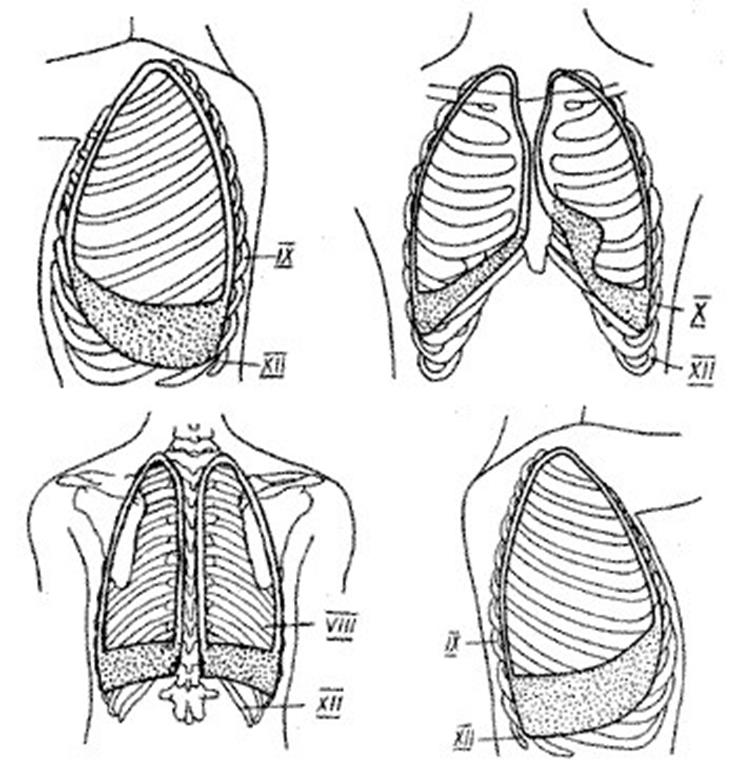

Анатомические изображения сегментов легких различных животных

Раздел: Другие животные